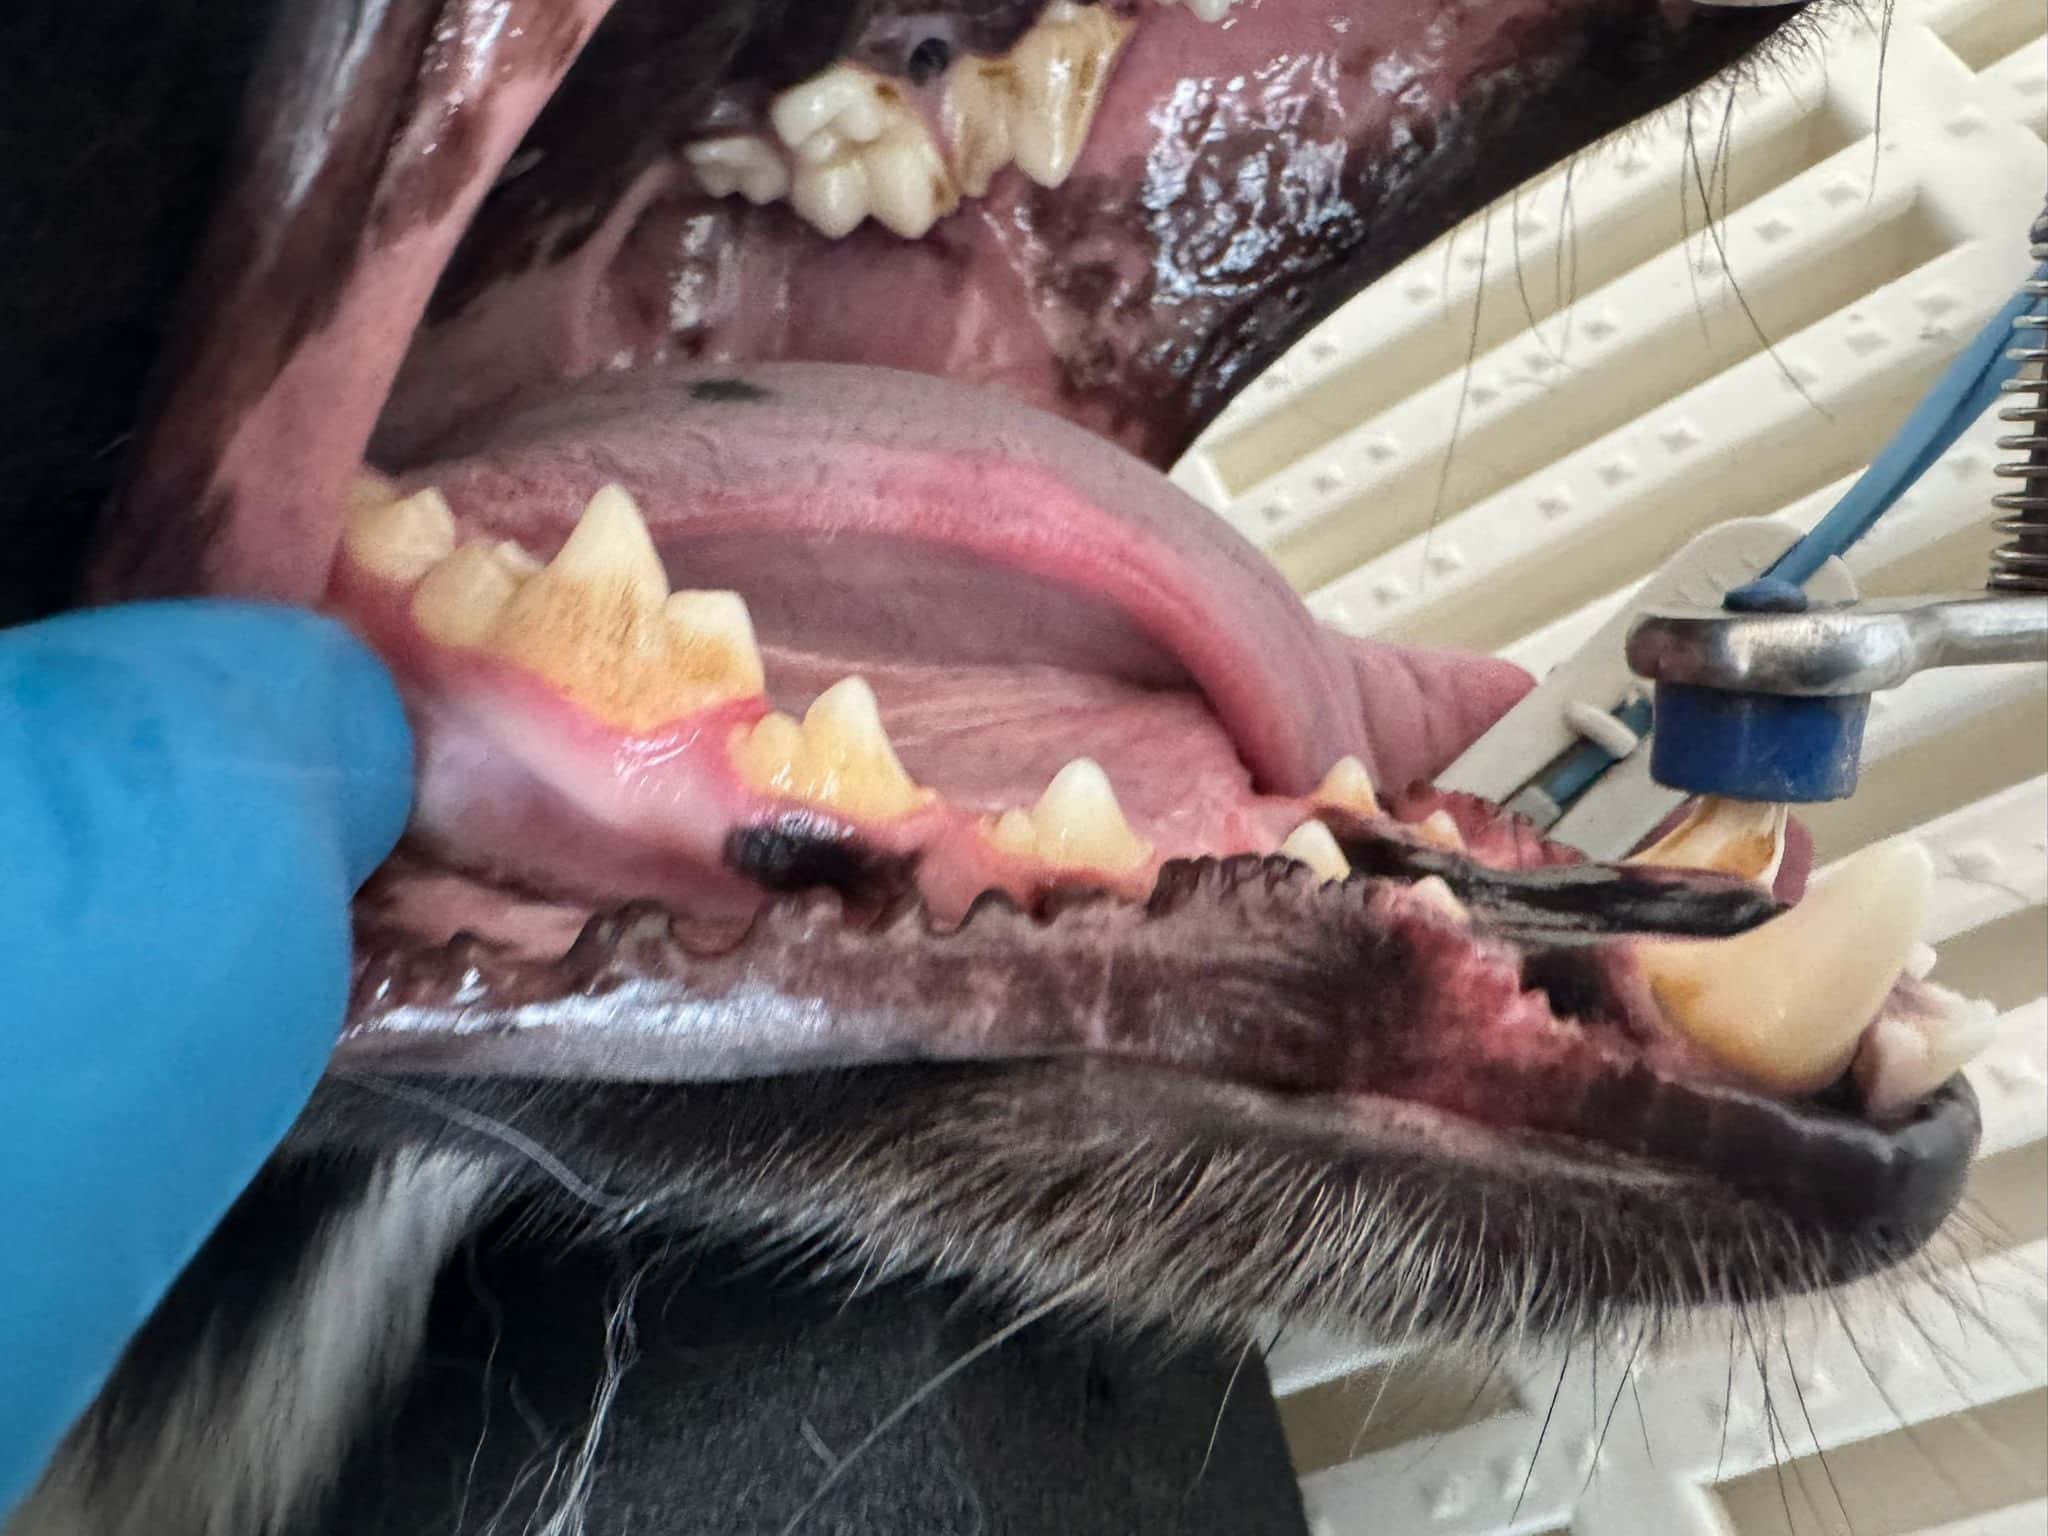

Beispielbilder vorher - nachher

Nachher

Beispielfotos unserer Patienten

Wir entfernen den Zahnstein vollständig und professionell